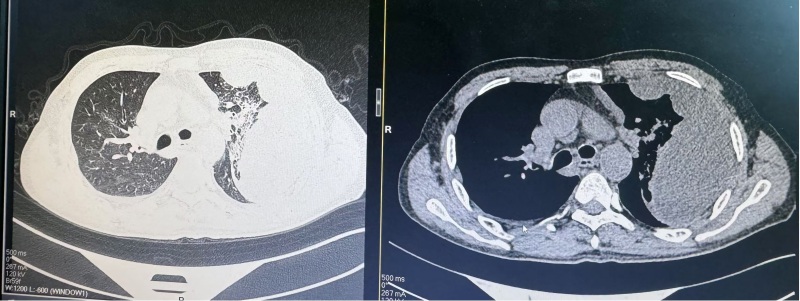

患者苏先生今年49岁,因“咳嗽、咳痰伴发热10天”就诊于我院呼吸与危重症医学科一病区,入院后完善胸部CT提示:两肺炎症改变,右肺多发结节,两侧胸腔积液,左肺病变伴包裹性胸腔积液合并肺膨胀不全。患者在胸水NGS、胸水脱落细胞病理检查后仍不能确定左肺病变性质,科室团队进行集体讨论之后拟行胸腔镜检查进一步明确诊断。在与患者及家属沟通后,决定实施内科胸腔镜手术。